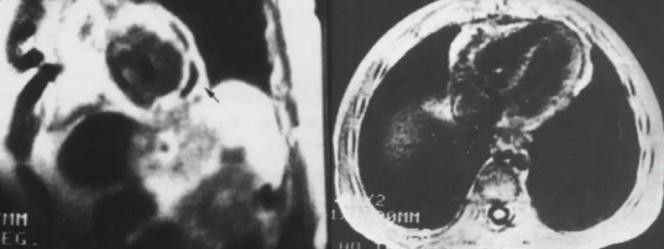

3.超声心动图 可见心包增厚、钙化,可发现心室容量减少,心房扩大,尤其左心房扩大较多见。